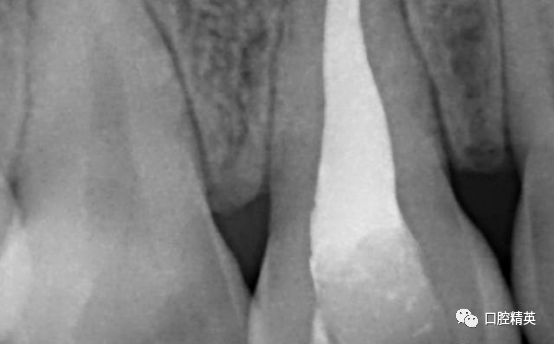

术后CBCT

术后两周拆线,复查X光片。

美学区软组织无退缩或外形改变。根尖区充填密实,根尖周组织初步愈合。记录牙体颜色变化。交代注意事项,4-6周复查。3-6个月完成美白及修复治疗。